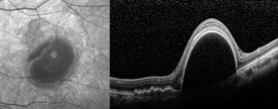

老王左眼檢查圖片

左眼調(diào)整用藥半個月后檢查圖片